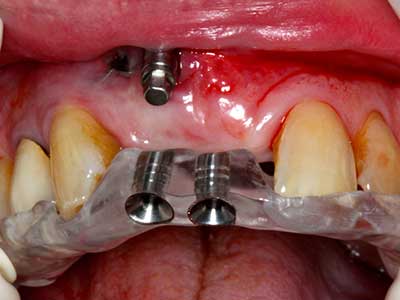

Fig. 17a: CT image of a growth-promoting osteotomy immediately adjacent to ...

Abb. 17b: the alveolar duct with nerve irritation (lateral and coronal view).

Fig. 18: Preparation of a cortical cover with the piezo bone saw (Piezomed, W&H).

Fig. 19: Surgical site after neurolysis and removal of osteoma.

Fig. 20: The removed bone cover is re-adapted and fixed with an osteosynthesis screw (KLS Martin, Tuttlingen).